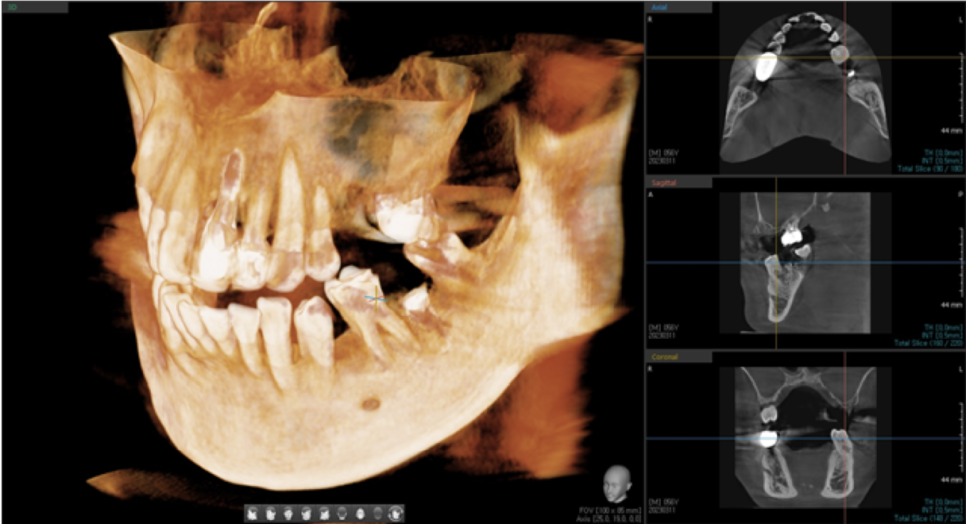

앞니 수술을 하기 위해서 3차원 CT 엑스레이 촬영을 했습니다.

CT 사진을 보며 적당한 위치를 선정하고, 임플란트의 길이와 두께를 정합니다.

뼈이식을 추가로 진행하였으며, 3개월 후에 보철을 올리기로 했습니다.